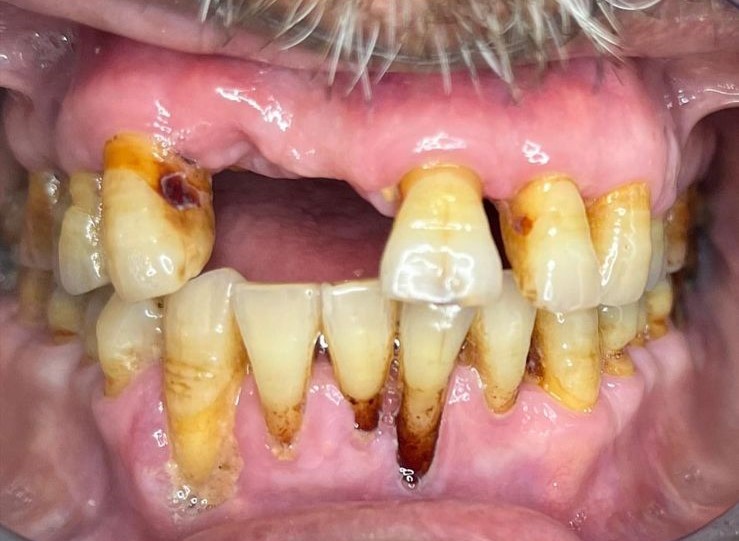

Before